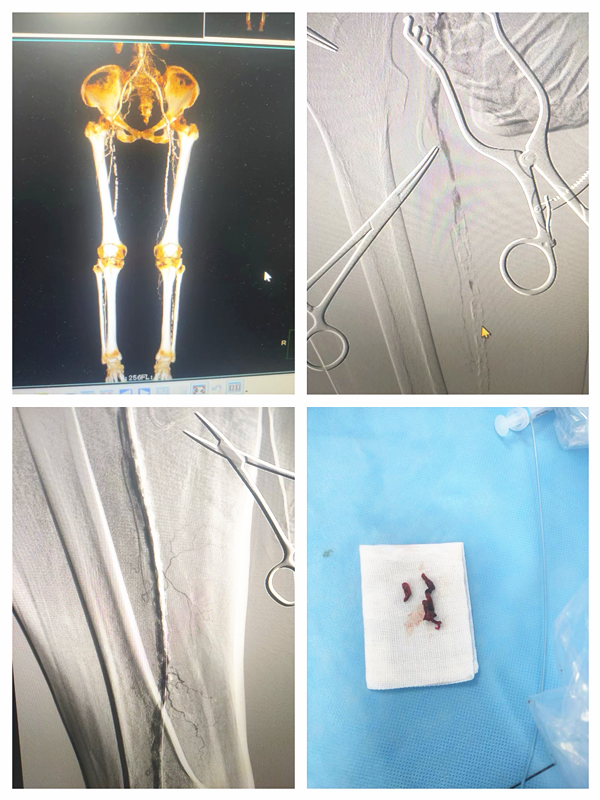

6月2日

一名63岁男性因右下肢发凉伴疼痛入住胸心血管外科,经完善检查后明确诊断为下肢动脉硬化闭塞症,胸心血管外科团队为患者行下肢动脉造影,经导管取栓术,取栓导管取出大量陈旧性血栓,复查造影腘动脉、胫腓干、胫前、胫后动脉及腓动脉通畅,患者下肢症状得到改善,立竿见影地解除了患者的病痛。